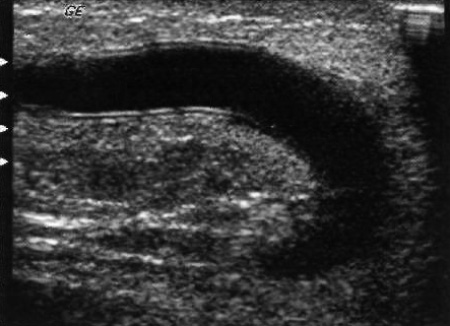

В норме шунт визуализируется как две параллельные эхогенные линии, расположенные непосредственно под кожей. Центр шунта – анэхогенный (фото 2).

Фото 2. Шунт в норме. Ультразвуковое изображение нормального шунта в режиме серой шкалы (стенки шунта эхогенные)